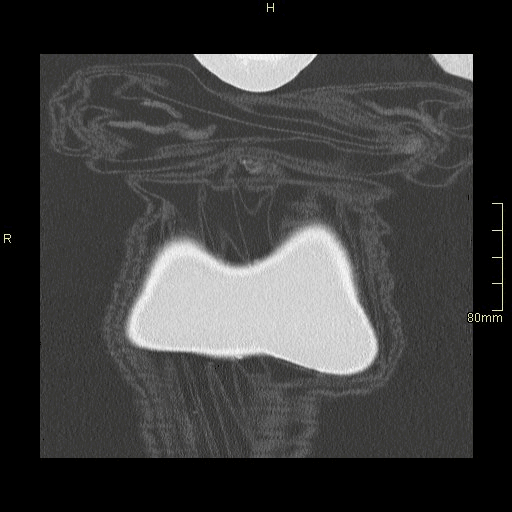

HRCT - Axial Prone Inspiration (Soft Tissue Window)

HRCT - Axial Supine Inspiration (Soft Tissue Window)

HRCT - Axial Supine Expiration (Soft Tissue Window)

HRCT - Axial Prone Inspiration (Lung Window)

HRCT - Axial Supine Inspiration (Lung Window)

HRCT - Axial Supine Expiration (Lung Window)

HRCT - Coronal Prone Inspiration (Lung Window)

HRCT - Coronal Supine Inspiration (Lung Window)

HRCT - Coronal Supine Expiration (Lung Window)